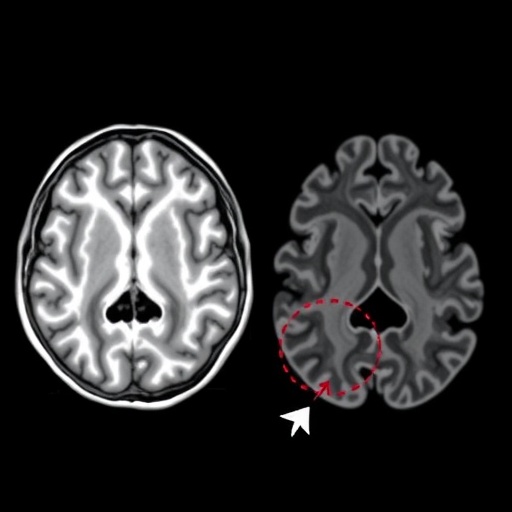

As we delve deeper into the implications of the research, it becomes evident that the combination of imaging glutamate levels and morphometric analysis reveals the nuances of brain development in preterm infants. By employing high-resolution MRI scans, the researchers could not only measure glutamate concentrations but also assess variations in hippocampal volume, surface area, and shape. These morphometric changes offer insights into how early brain development may influence long-term neurocognitive abilities, establishing a tangible connection between physiology and psychological health.

One particularly interesting finding from Xu’s study is the specific alterations in hippocampal morphology observed in preterm infants with low birth weight. The research has indicated that these infants often display a reduction in hippocampal volume compared to their term-born counterparts. This reduction might signal impaired neurogenesis and increased vulnerability to behavioral and cognitive deficits as they age. By illuminating these early physiological changes, the study encourages ongoing exploration into targeted neuroprotective strategies that could foster cognitive development in at-risk populations.

The methodology employed within this study showcases the remarkable capabilities of modern imaging technologies. MRI has progressed significantly, allowing researchers to explore the structure and function of the brain in unprecedented detail. This non-invasive approach avoids the complications and risks associated with other imaging modalities, such as X-rays or CT scans, thereby providing a safe option for examining delicate neural structures in vulnerable populations, such as preterm infants.